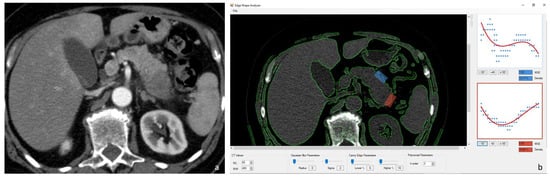

Two radiologists, with 10 and 15 years of experience in abdominal imaging, analyzed the MDCT scans and selected through consensus two CT slices of the nonenhanced scan: one that depicted the tumor and one with normal pancreatic parenchyma. The images were annotated for further reference (Figure 1). “In-house” postprocessing software was used to quantify the amount of parenchymal surface nodularity on CT images as a continuous numerical value. The software used a Canny edge detector operator to identify a set of pixels as the pancreatic border defined as the average boundary line. Selecting a region of interest, the software provided a measure of the deviation of the analyzed pancreatic border from the smooth-fitted line. The root of these values is the “pancreatic margin score” (PMS) [,].

Figure 1.

Postcontrast arterial MDCT axial image of adenocarcinoma of the tail of the pancreas (a). Screenshot of the GUI of the software used (b) with blue box positioned on normal parenchyma and the red box positioned on an adenocarcinoma of the tail of the pancreas. The graphic output of the results from the Canny edge detection and the subsequent average boundary line for both the boxes selected are visible.

Pancreatic borders were sampled, drawing two boxes on CT slices with normal and tumoral parenchyma: the two boxes were kept constant in size in the different images and between different patients. The software automatically detected the pancreatic edge compared to the adjacent adipose tissues and provides as a graphic output the results from the Canny edge detection and the subsequent average boundary line together with all the relative results from the root mean square deviation calculation for an immediate comparison (Figure 1).